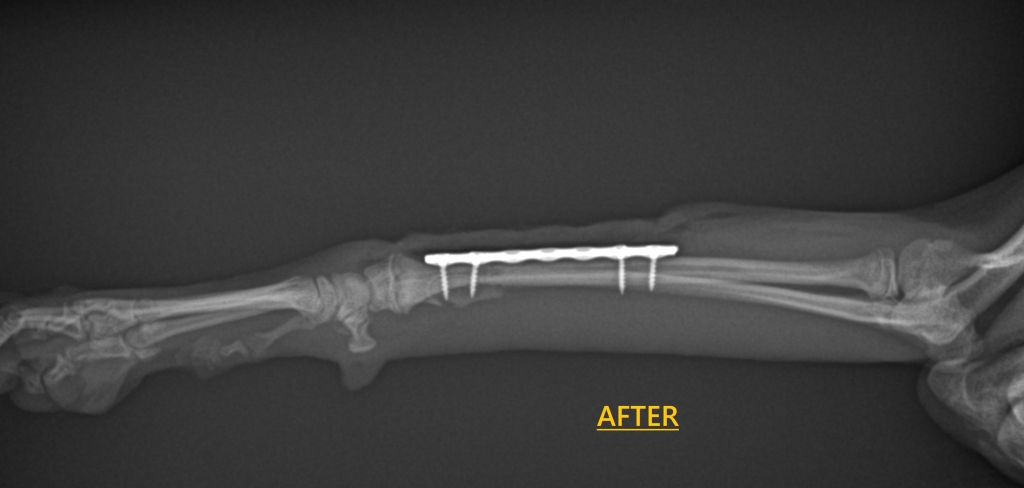

今回はチタン製プレート(1.0mmスクリュー)を用いて整復固定を行いました。

術後は順調に回復しています。

小さな体でも、適切な固定を行うことで

しっかりと治癒が期待できます。